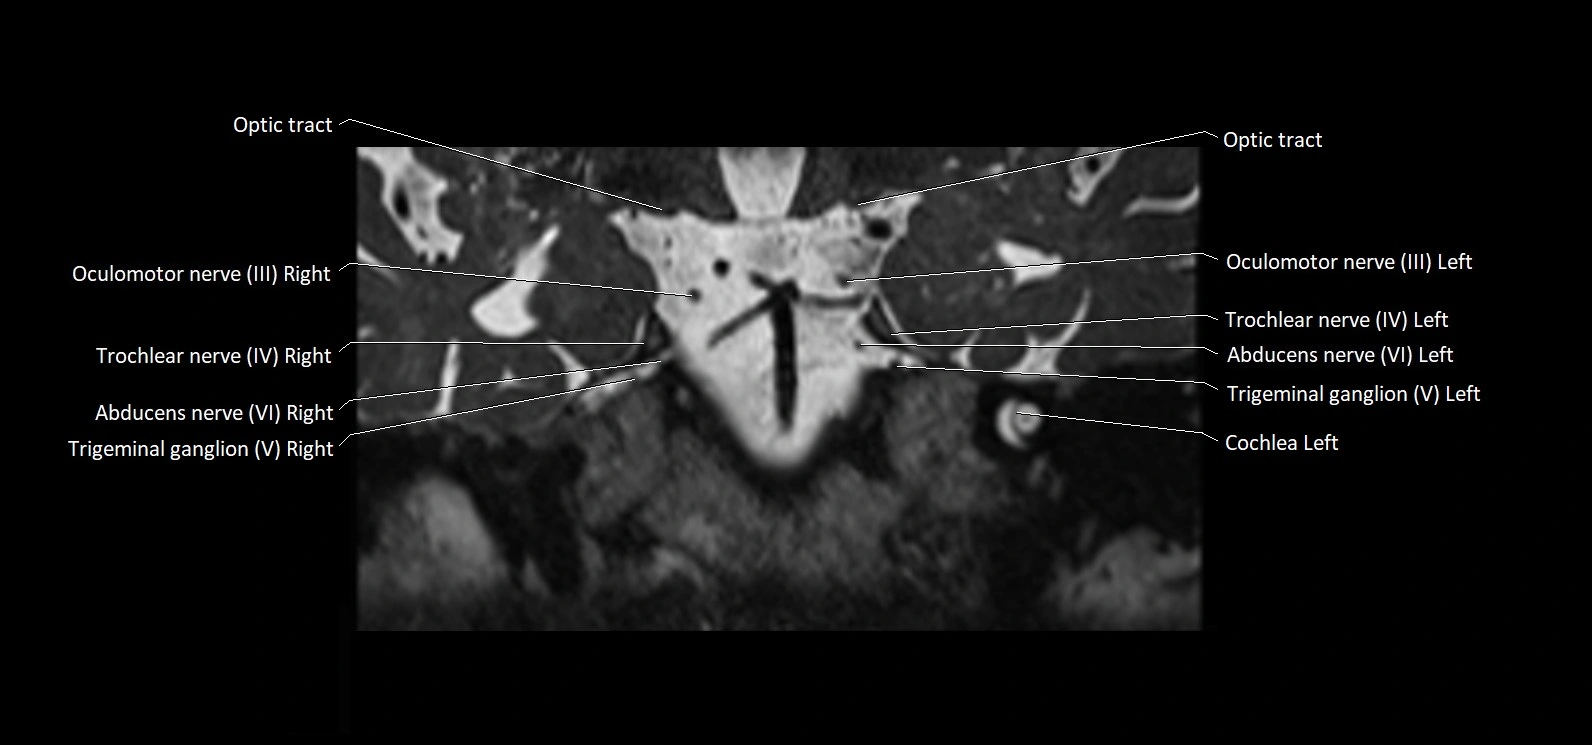

MRI Appearance

• The abducens nerve is a small, thin, linear structure

• Best visualized on high-resolution T2-weighted 3D MRI sequences (e.g., FIESTA or CISS)

• Seen as a hypointense (dark) line running from the brainstem at the pontomedullary junction, traversing the prepontine cistern, and entering Dorello’s canal under the petrosphenoidal ligament, then into the cavernous sinus, and finally the orbit

• May be challenging to visualize in standard MRI due to its small size

• Pathology may be inferred by absence, displacement, or enhancement of the nerve

MRI images

image